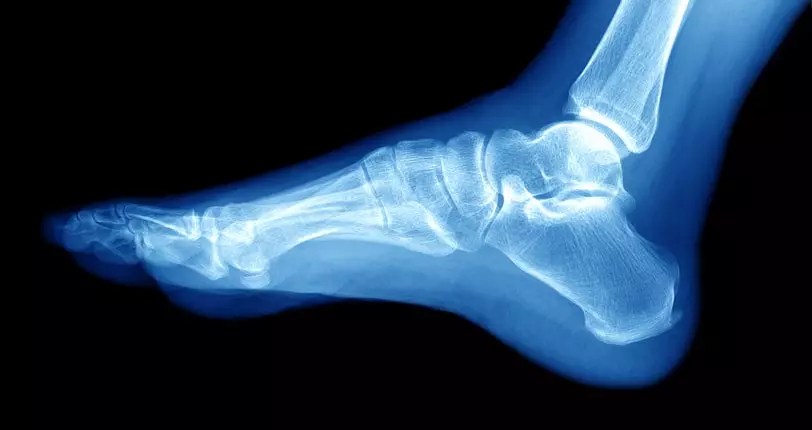

If you’ve ever stepped on a large stone and sprained your ankle, you know how painful it can be almost instantly. At that moment, you

The American College of Sports Medicine reports that 25,000 ankle sprains happen daily, accounting for nearly half of all sports-related injuries. Ankle fractures are less